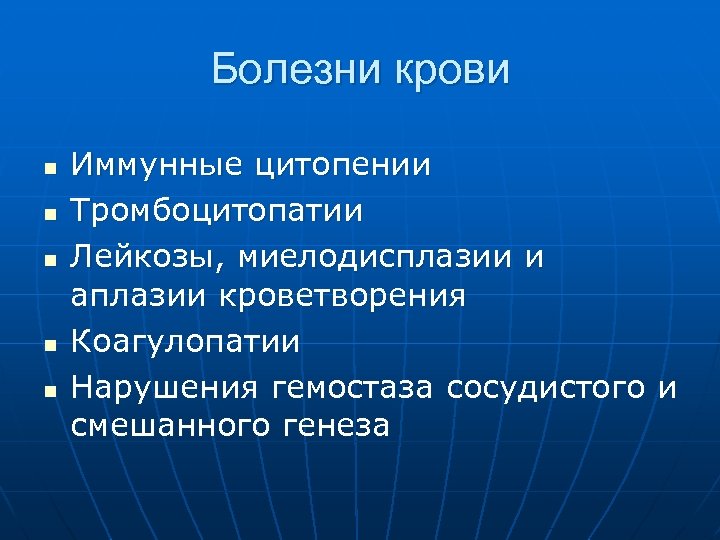

Болезни крови n n n Иммунные цитопении Тромбоцитопатии Лейкозы, миелодисплазии и аплазии кроветворения Коагулопатии Нарушения гемостаза сосудистого и смешанного генеза